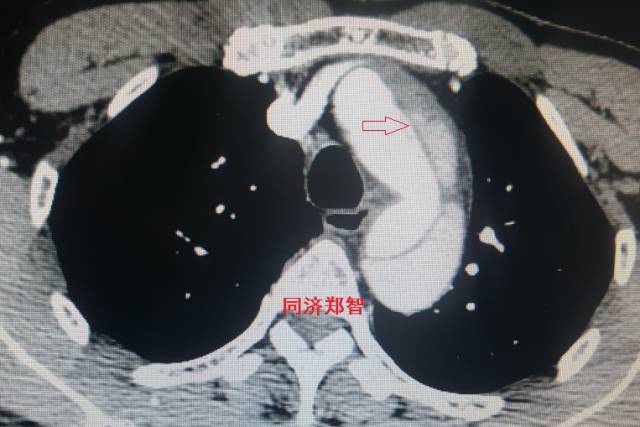

平扫CT提示主动脉弓层面及右肺动脉层面均可见主动脉血管腔内的内膜片影(红色箭头所示),CTA显示为A型主动脉夹层。

图8-11